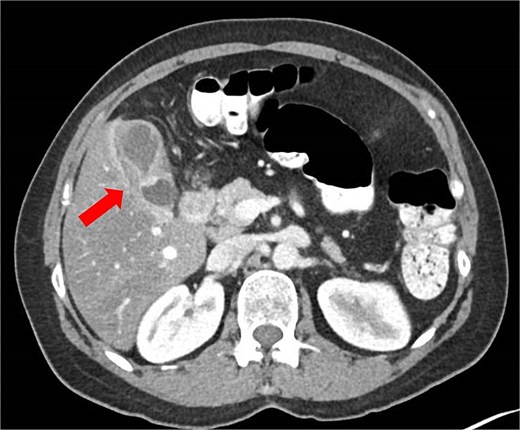

Initial abdominal ultrasonography was inconclusive. A follow-up fasting ultrasound revealed vascular, thickened content within the gallbladder, suggestive of either cholelithiasis or malignancy. The liver appeared moderately fatty without enlargement or biliary ductal dilatation. A contrast-enhanced computed tomography (CT) scan demonstrated gallbladder wall thickening and a luminal constriction at mid-body, producing a classic “hourglass” appearance (Fig. 1).

Abdominal CT scan showing an ‘hourglass’ appearance of the gallbladder (arrow).